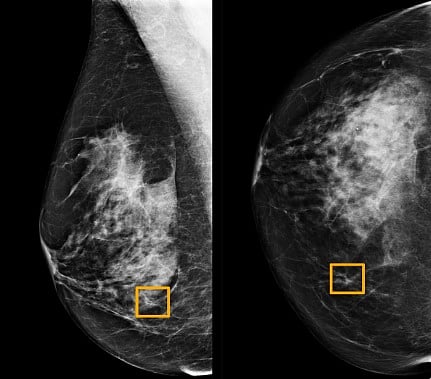

ثم قارنوا توقعات النظام بالنتائج الفعلية لمجموعة تشمل 25856 تصويرًا بالأشعة السينية للثدي في بريطانيا و3097 في الولايات المتحدة.

وأظهرت الدراسة أن نظام الذكاء الاصطناعي تمكّن من تحديد الإصابة بالسرطان بدرجة مماثلة لدقة خبراء الأشعة؛ في حين خفض عدد النتائج الإيجابية الخاطئة بواقع 5.7% في المجموعة الموجودة في الولايات المتحدة وبنسبة 2.1% في تلك الكائنة في بريطانيا.

وخفض كذلك النتائج السلبية الخاطئة، التي صنفت الاختبارات خطأ على أنها طبيعية، 9.4% في المجموعة الأمريكية و2.7% في المجموعة البريطانية.